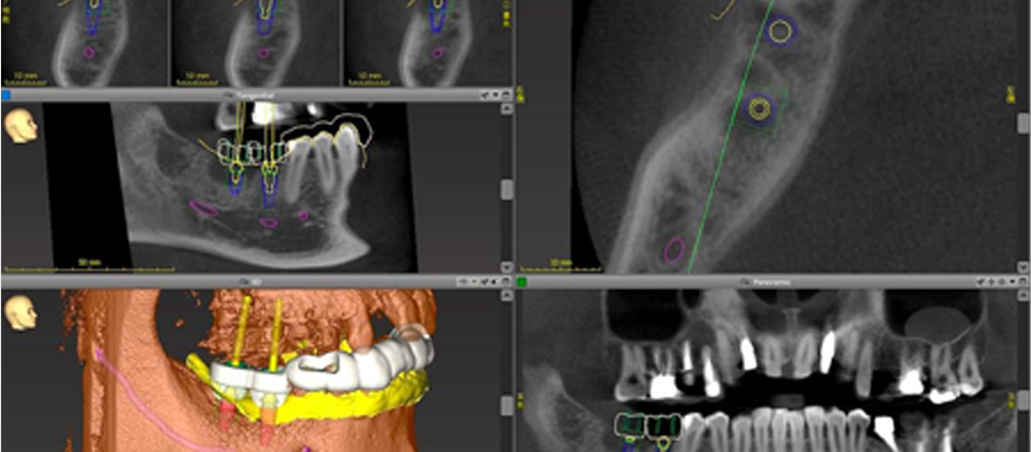

当院では、CTなどの先進設備と科学的根拠に基づいた診断により、長く安心して使えるインプラント治療を行っています。

- CTによる精密診断

- かみ合わせも考慮した治療計画

- 補綴専門医が担当。難しい症例にも対応

こうした設備とノウハウにより、高い成功率と安全性を両立させたインプラント治療を実現しています。